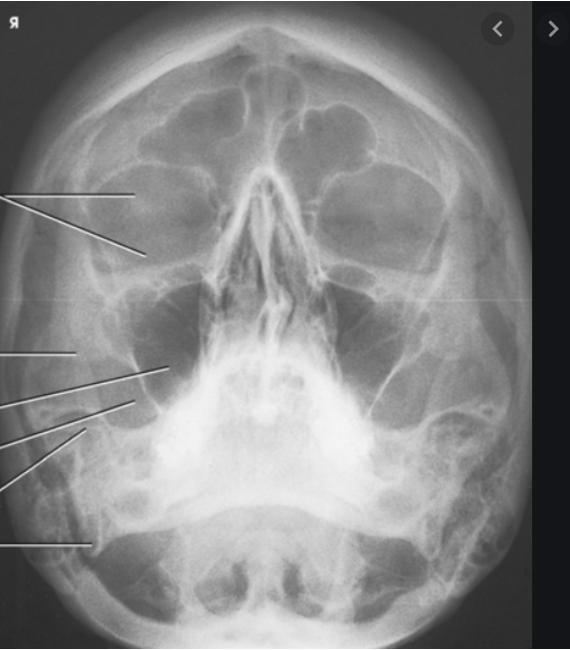

PA axial of skull - Caldwell method

PA axial skull - Caldwell Method